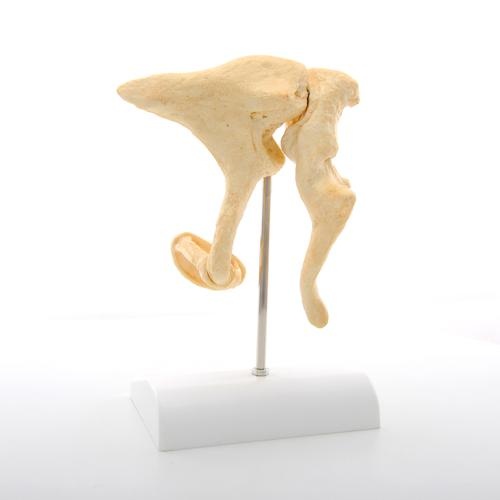

Flexibel montierte Abformung der menschlichen Wirbelsäule in hervorragender BONElikeTM Qualität

mit originalgetreuer Wiedergabe aller anatomischen Details und realem Gewicht.

Mit männlichem Becken und Hinterhauptschuppe.

Hinterhauptschuppe und Atlas sind einzeln abnehmbar.